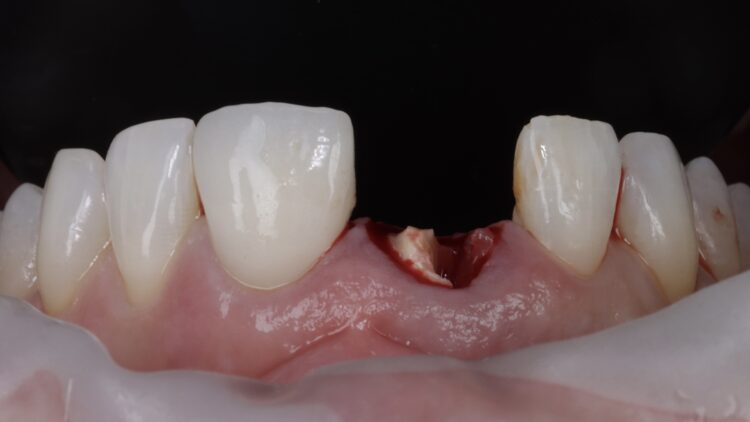

On the day of surgery, the post crown was removed, and the tooth sectioned to ease extraction while preserving the buccal plate. Forceps were used to deliver the fragments, with extensions to simplify pick-up (Hu-Friedy). The granulation tissue was removed using a Lucas curette.

The surgical guide was checked in the mouth, ensuring it was fully seating and not in contact with the adjacent teeth.